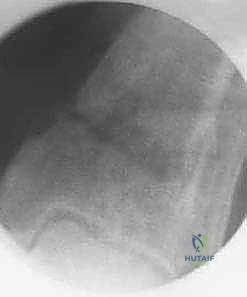

* تنظيف المفصل بالمنظار (Arthroscopy) لإزالة الزوائد العظمية أو الغضاريف الممزقة.